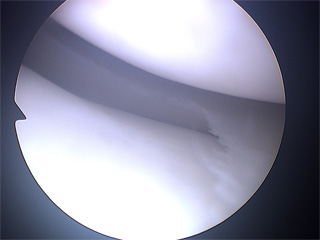

Die Kniearthroskopie ist eine chirurgische Technik, die einen Einblick in das Innere des Knies mit seinen kleinen Gelenkstrukturen ermöglicht, ohne einen größeren Eingriff vornehmen zu müssen. Es werden über zwei kleine Hautschnitte mit weniger als 6mm Länge auf beiden Seiten der Patellarsehne Präzisionsinstrumentarium und eine Kameralinse (Optik) eingeführt. Über die Fiberglasoptik wird das Bild auf einem Monitor dargestellt, so dass gemeinsam mit dem wachen Patienten in Spinalanästhesie (Rückenmarks-Narkose) die inneren Strukturen gesehen und das Vorgehen verfolgt werden kann.

Bei der Durchführung jeglicher Kniearthroskopie sollte mit einer kompletten, systematischen Spiegelung des gesamten Kniegelenks begonnen werden, da Läsionen entdeckt werden können, die vorher bei bildgebenden Verfahren (MRT/CT/Röntgen) nicht gesehen worden sind.